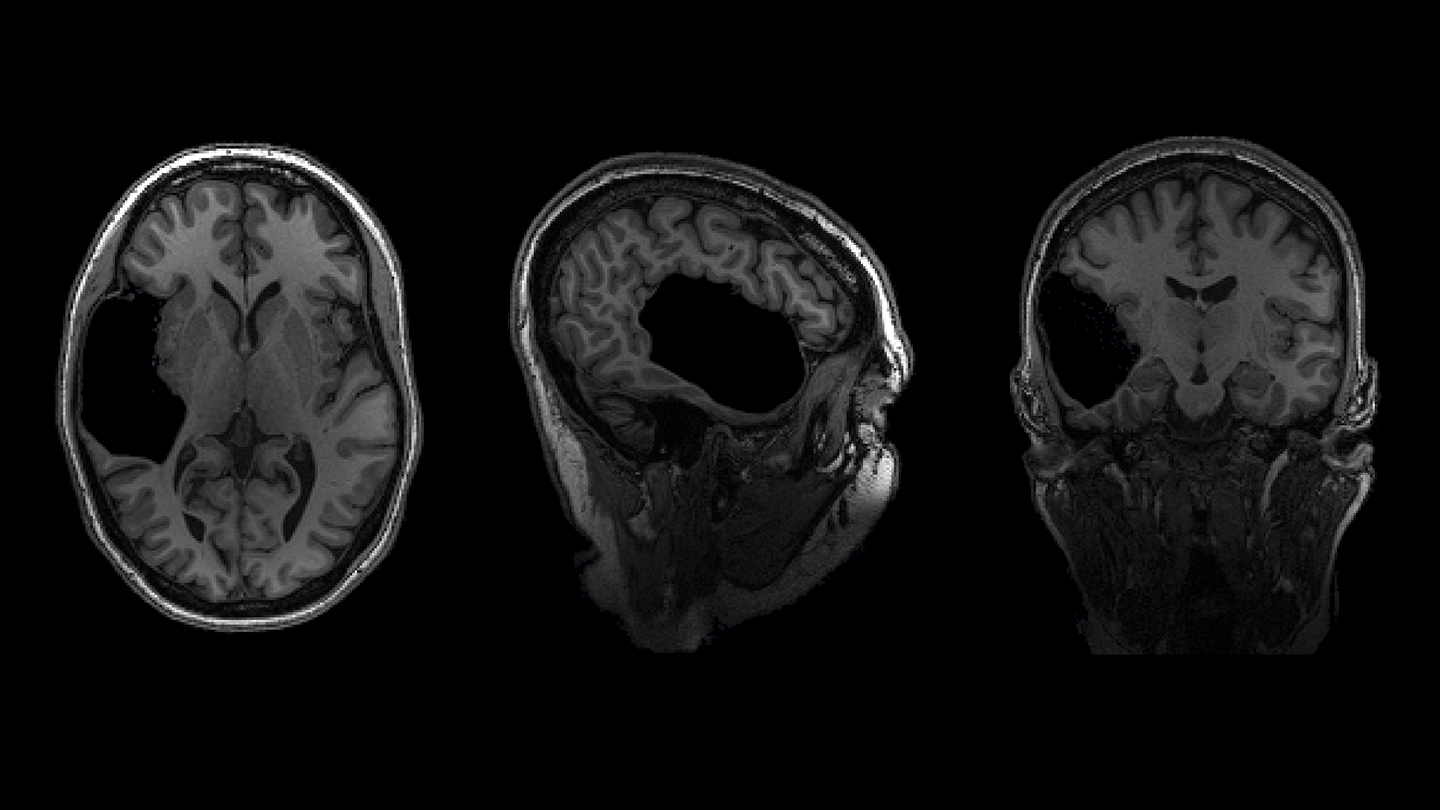

Elyse G. found out she lacked most of her left temporal lobe when she was 25 years old. The brain region is typically crucial for speech and language — but until her brain was scanned (three views shown), no one knew Elyse was missing hers.

Looking at her brain scans is a different story. It’s as if someone has knocked over a bottle of ink. The darkness pools inside her skull near her left ear, a puddle of fuliginous black. Inside the splotch, there’s no white matter or gray matter, no blood vessels or tissue at all.

Elyse says you don’t have to be a neurosurgeon to spot what’s different about her brain: “There’s a big honking piece missing!”

Scientists can’t say exactly how it happened. It’s possible that sometime long ago, perhaps due to a stroke before or shortly after birth, a portion of Elyse’s brain died and then ultimately disappeared, leaving behind only liquid — brain tissue swapped for a fluid-filled void. Her sister has one too.